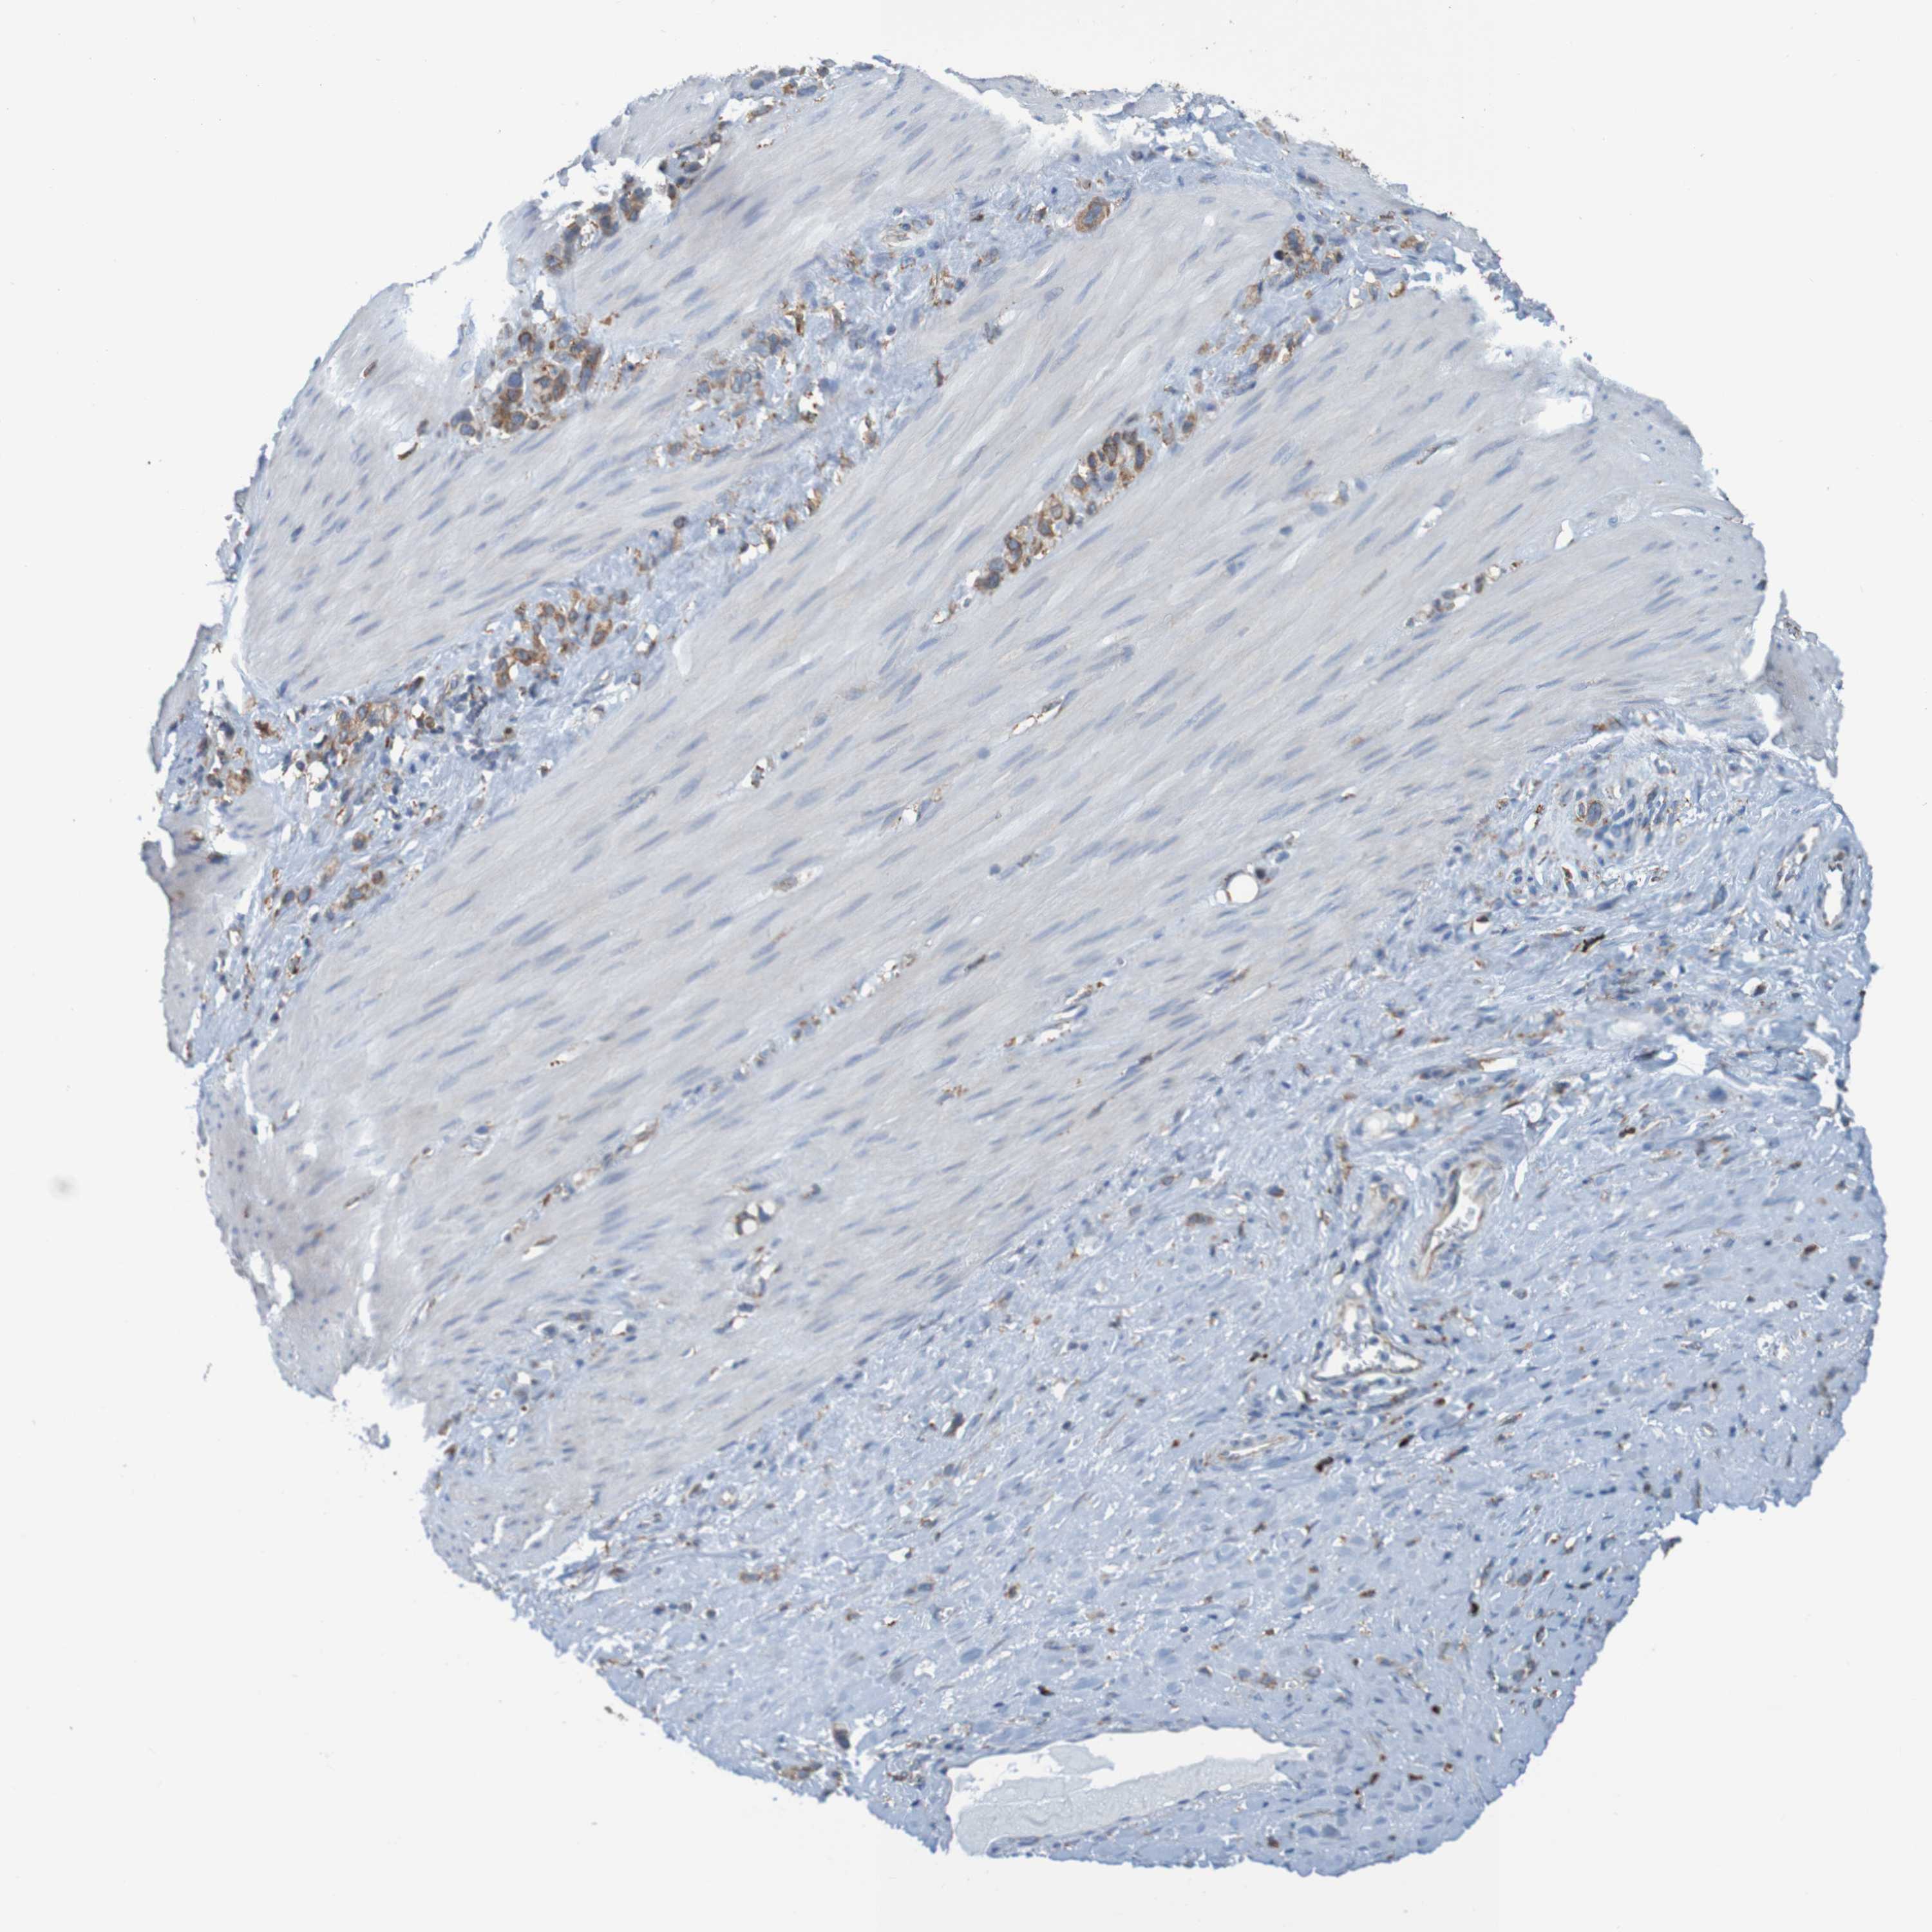

STOMACH CANCER - Protein expressioni

A mouse-over function shows sample information and annotation data. Click on an image to view it in a full screen mode. Samples can be filtered based on level of antibody staining by selecting one or several of the following categories: high, medium, low and not detected. The assay and annotation is described here.

Note that samples used for immunohistochemistry by the Human Protein Atlas do not correspond to samples in the TCGA dataset.

Antibody stainingi

Antibody staining in the annotated cell types in the current human tissue is reported as not detected, low, medium, or high, based on conventional immunohistochemistry profiling in selected tissues. This score is based on the combination of the staining intensity and fraction of stained cells.

Each image is clickable and will lead to virtual microscopy that enables deeper exploration of all samples and also displays staining intensity scores, fraction scores and subcellular localization as well as patient and tissue information for each sample.

Antibody HPA011276

Antibody HPA017062

Staining

High

Medium

Low

Not detected

Intensity

Strong

Moderate

Weak

Negative

Quantity

>75%

75%-25%

<25%

None

Location

Nuclear

Cytoplasmic/membranous

Cytoplasmic/membranous,nuclear

Adenocarcinoma, NOS

Adenocarcinoma, High grade